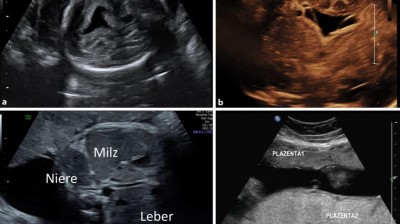

Zytomegalievirusinfektionen In Der Schwangerschaft Gynakologie Geburtshilfe Universimed Medizin Im Fokus